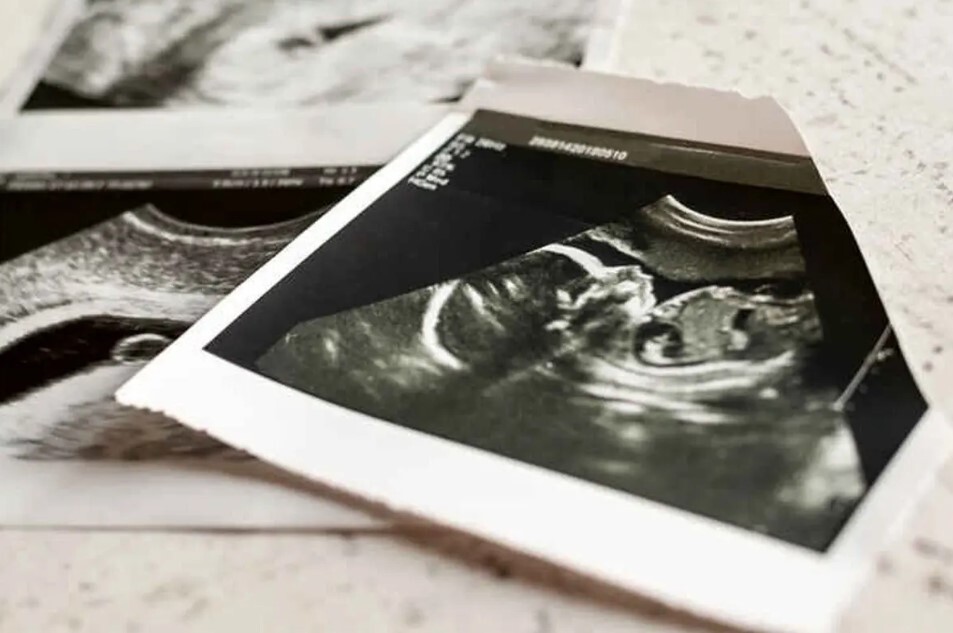

مبالغ نجومی برای سقط جنین غیرقانونی؛ از ۷۰ تا ۱۵۰ میلیون!

رویداد ۲۴| طبق گفته یک ماما که سقط غیر قانونی انجام میدهد، اگر همه چیز نرمال باشد برای سقط جنین زیر سه ماه تقریبا ۷۰ میلیون و بالای ۴ ماه آن هم تنها یک هفته بیشتر از ۴ ماه با مبلغ ۱۵۰ میلیون کار را انجام میدهد.

یک پزشک عمومی در مورد هزینه این عملها میگوید که هزینه سقط جنین غیرقانونی تا ۴ ماه ۱۲۰ میلیون تومان است. البته افرادی هم هستند که چنین پولی ندارند، اما به این خاطر که ممکن است جانشان به خطر بیافتد با هزینه کمتر هم حاضر به انجام کار میشوم. اما اگر افرادی با تمکن مالی بالا برای این کار مراجعه کنند، بیش از ۱۲۰ میلیون از آنها میگیرم.